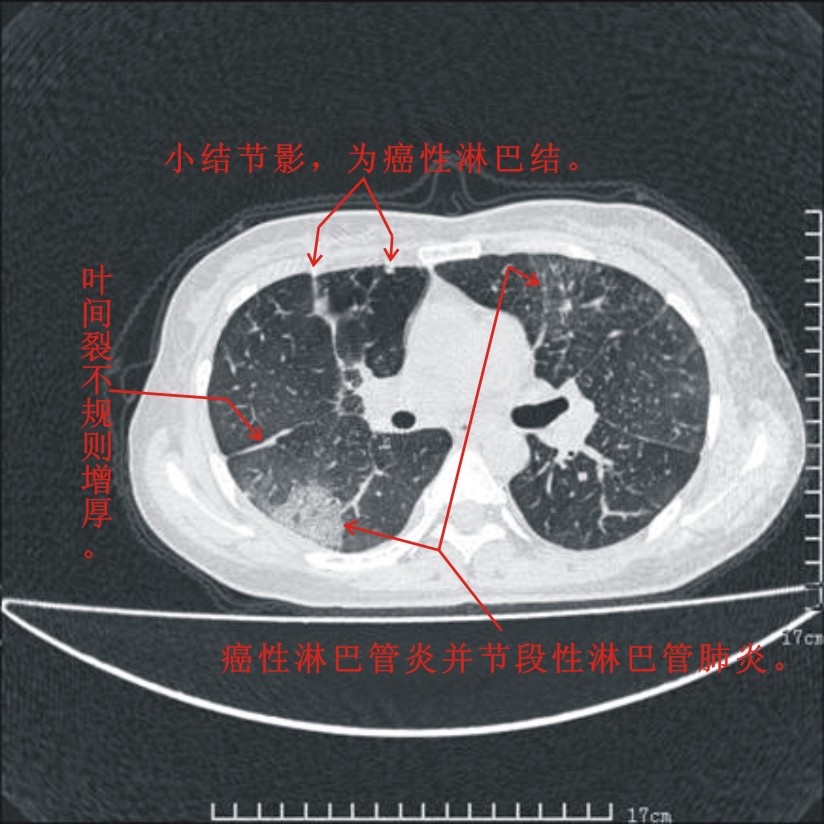

结合病史:认为是典型肺部癌性淋巴管炎、淋巴结转移。请看图解。

肺癌性淋巴管炎征象分为主要征象及合并征象,主要征象包括:

1、近肺门支气管血管周围间质结节状增厚;

2、小叶间隔结节状增厚;

3、小叶中央间质结节状增厚;

4、胸膜下间质结节状增厚。

合并征象为:纵隔淋巴结增大,胸腔积液,肺多发随机分布的小结节等。